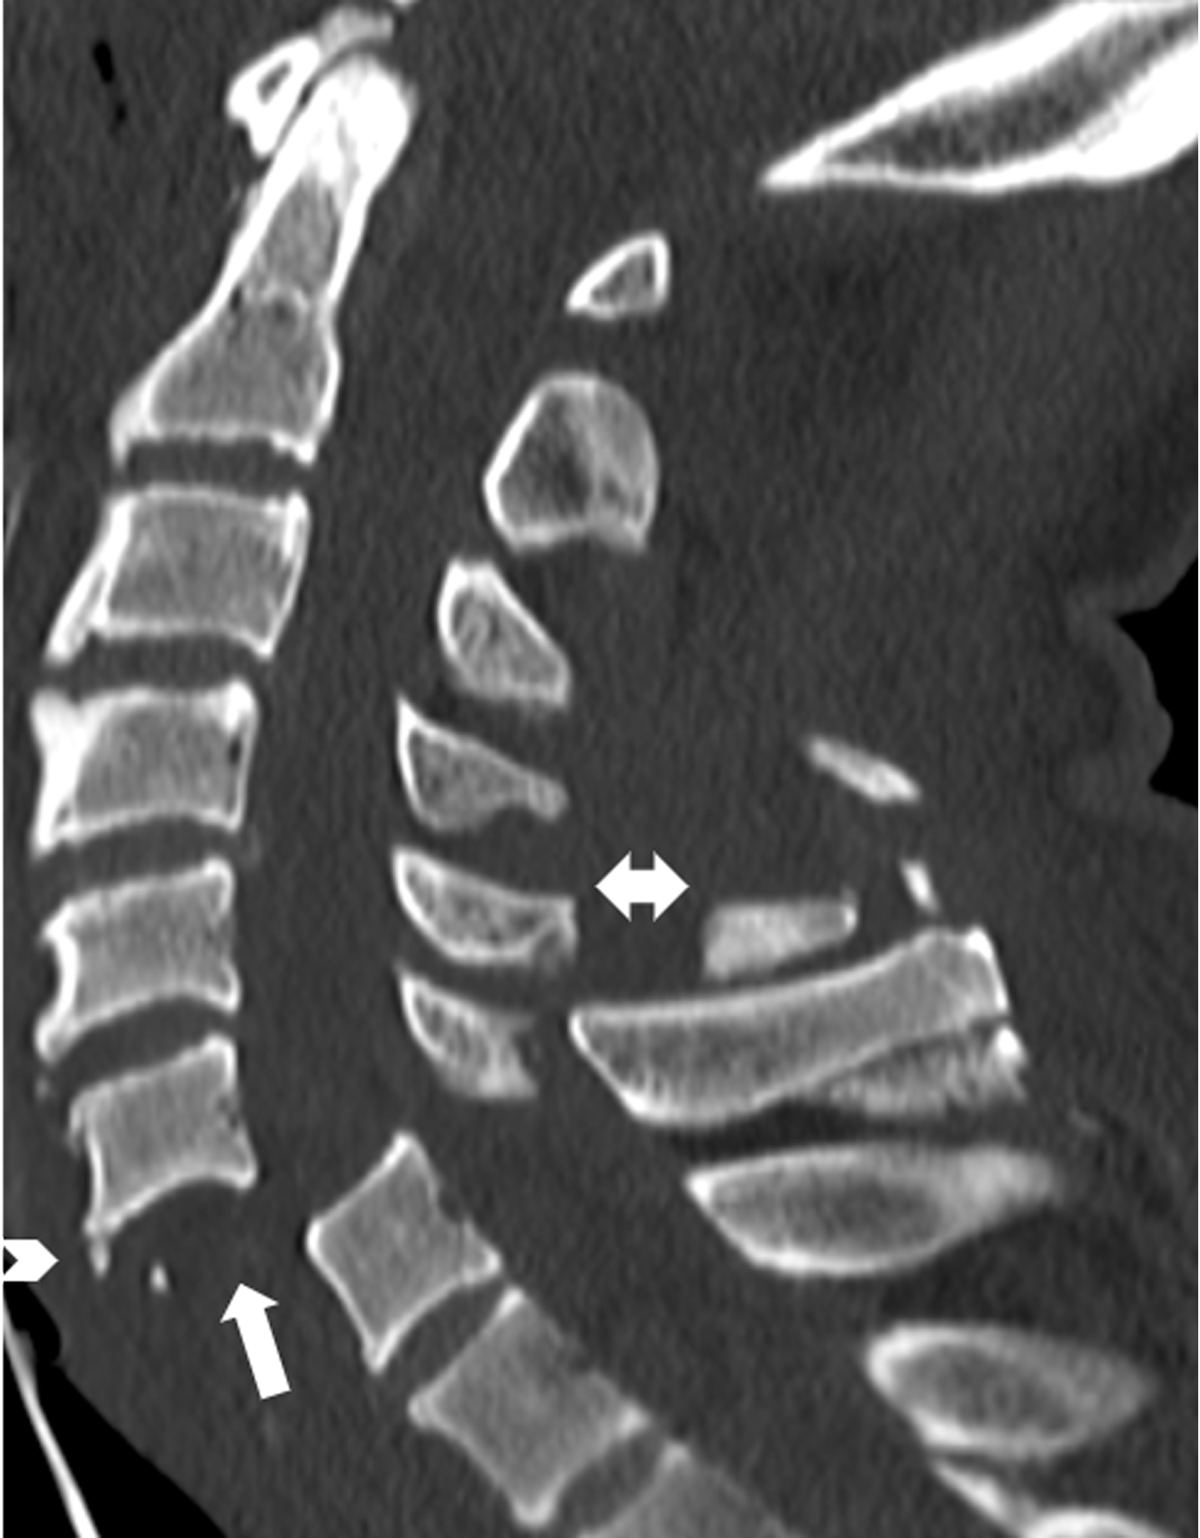

Figure 2

Floating vertebra sign and teardrop sign.

Sagittal CT cervical spine of a 77-year-old man following a high energy motor vehicle accident shows 100% translation of the C6 on C7 vertebral bodies, which is consistent with a grade IV anterolisthesis. The appearance of a “floating vertebra” (upward pointing arrow) is associated with bilateral facet joint dislocation and injury to the posterior ligamentous complex. In addition, there are fractures involving the C5 and C6 spinous processes (double head arrow). The mechanism of injury is secondary to forceful muscle contraction, transmitted through the supraspinous ligaments. The tremendous contraction force produces the avulsion fractures of the spinous process known as clay-shoveler fracture. Note the presence of a tiny anterior “teardrop” fracture at the anterior and inferior aspect of the C6 vertebral body (arrow head).